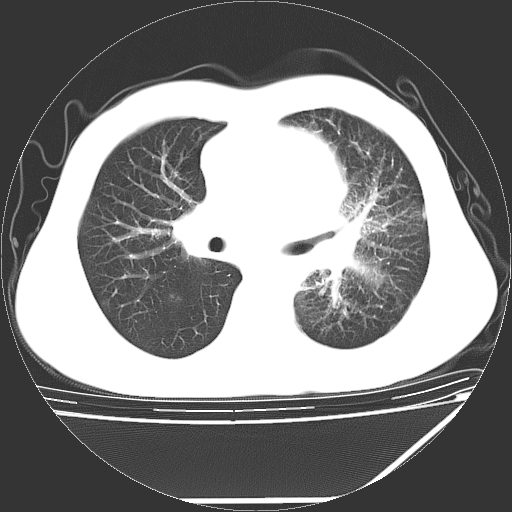

男,13岁,咳嗽、咳痰伴发热一周。

中上纵隔见多枚淋巴结肿大,部分相互融合成团片,左肺门增大,上叶支气管变窄,肺内多处斑片状 索条状及棉絮状致密影。临床“男,13岁,咳嗽、咳痰伴发热一周。”首先考虑:原发综合征!不除外淋巴瘤可能!

纵隔多发肿大淋巴结,部份有融合改变。双肺血管气管束增厚,以肺门为中心向外周散发,以左肺下叶为明显。考虑淋巴瘤可能性大。不除外原发综合征。

中上纵隔见多枚淋巴结肿大,部分相互融合成团片,左肺门增大,上叶支气管变窄,左肺支气管血管束增粗,可见磨玻璃样影。临床“男,13岁,咳嗽、咳痰伴发热一周。”首先考虑:淋巴瘤可能性大!

左肺野见淡片状影,病因整体多考虑结核

单纯看片子感觉左侧肺通气不畅,而不像肺内病变引起的纵隔病变。而且纵隔及左肺门都有淋巴结增大。首先还是考虑一下结节病,不排除淋巴瘤!!!